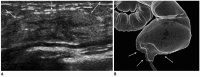

Breast metastases from extramammary malignancies are uncommon. The most common sources are lymphomas/leukemias and melanomas. Some of the less common sources include carcinomas of the lung, ovary, and stomach, and infrequently, carcinoid tumors, hypernephromas, carcinomas of the liver, tonsil, pleura, pancreas, cervix, perineum, endometrium and bladder. Breast metastases from extramammary malignancies have both hematogenous and lymphatic routes. According to their routes, there are common radiological features of metastatic diseases of the breast, but the features are not specific for metastases. Typical ultrasound (US) features of hematogenous metastases include single or multiple, round to oval shaped, well-circumscribed hypoechoic masses without spiculations, calcifications, or architectural distortion; these masses are commonly located superficially in subcutaneous tissue or immediately adjacent to the breast parenchyma that is relatively rich in blood supply. Typical US features of lymphatic breast metastases include diffusely and heterogeneously increased echogenicities in subcutaneous fat and glandular tissue and a thick trabecular pattern with secondary skin thickening, lymphedema, and lymph node enlargement. However, lesions show variable US features in some cases, and differentiation of these lesions from primary breast cancer or from benign lesions is difficult. In this review, we demonstrate various US appearances of breast metastases from extramammary malignancies as typical and atypical features, based on the results of US and other imaging studies performed at our institution. Awareness of the typical and atypical imaging features of these lesions may be helpful to diagnose metastatic lesions of the breast.